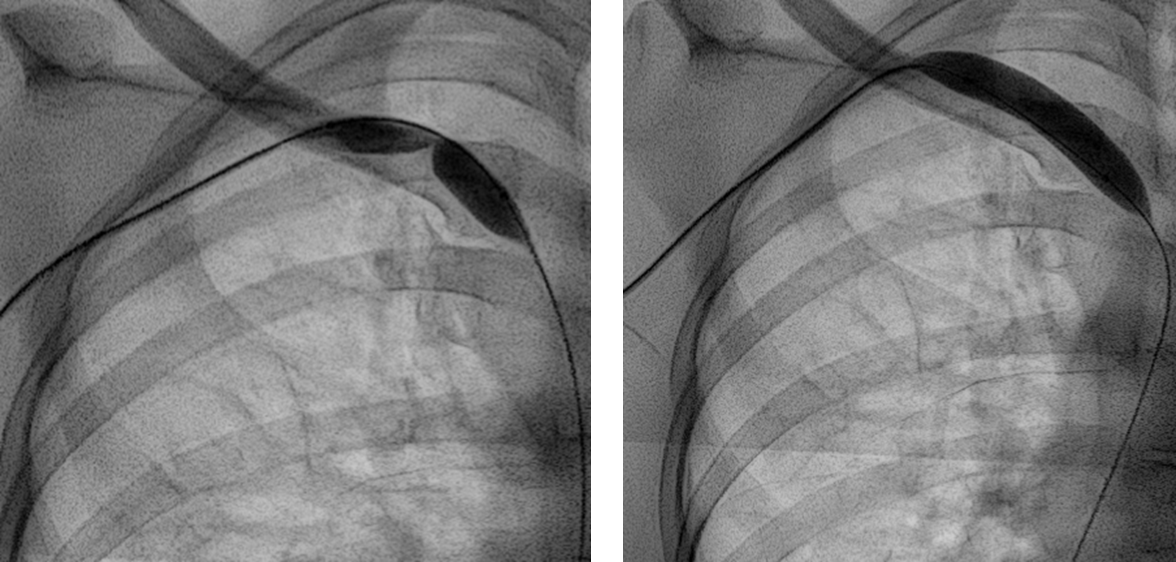

경피적 혈관성형술이란 피부를 미세 절개한 뒤, 직접 혈관으로 접근해서 좁아진 혈관을 확장해주는 시술입니다.